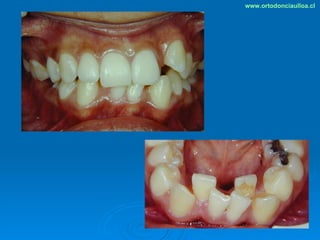

Este documento presenta dos casos clínicos de pacientes que recibieron tratamiento de ortodoncia. El primer caso fue de una paciente femenina de 14 años con apiñamiento dental y mordida cruzada que fue tratada mediante extracción de premolares y alineamiento dental. El segundo caso fue de un paciente masculino de 14 años con clase II esqueletal y desarmonía dentomaxilar que fue tratado con extracción de premolares y corrección de mordida. Ambos casos mostraron mejoría después de 3 años de tratamiento.